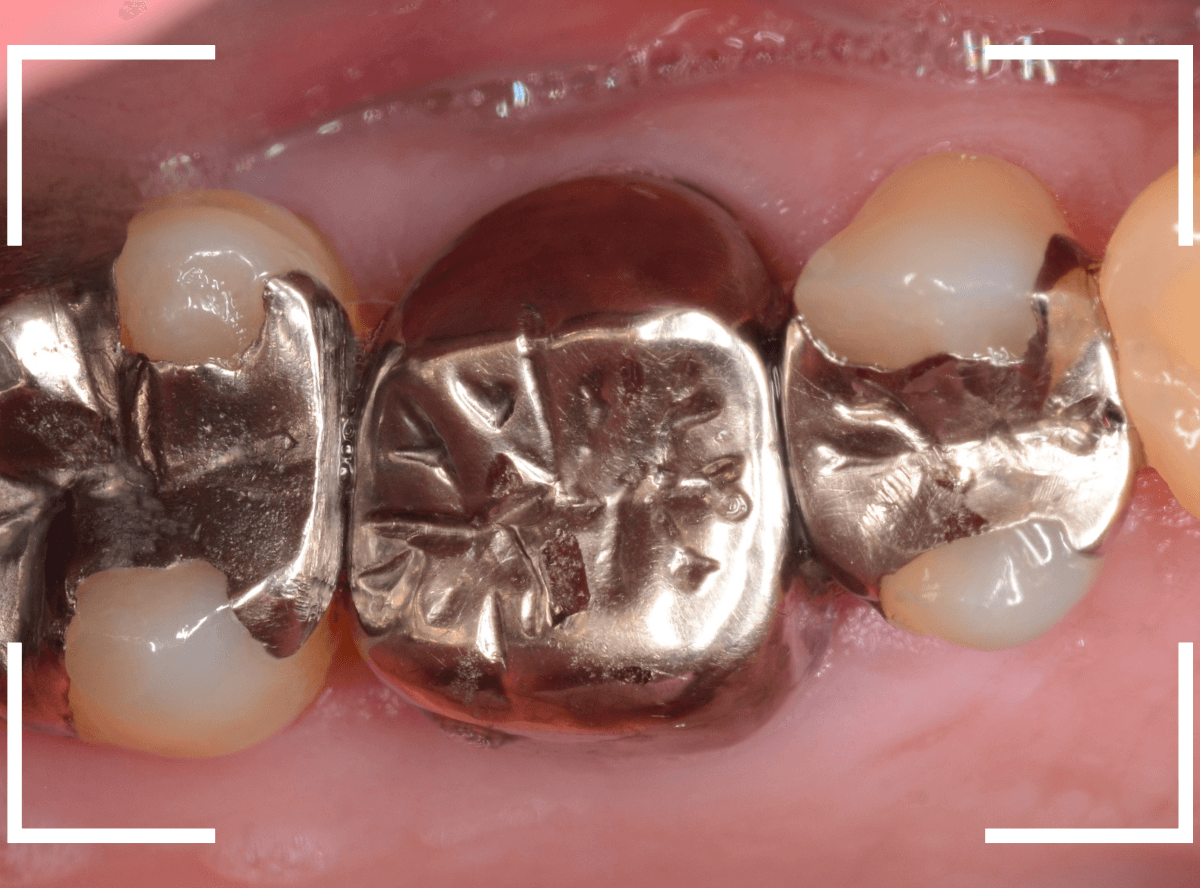

Case.20 メタル・インレーとメタル・クラウンをジルコニアにやり替え

「下の奥歯の銀歯を白くしたい」というご希望の患者さんです。

メタル・インレーとメタル・クラウンが入っていますね。